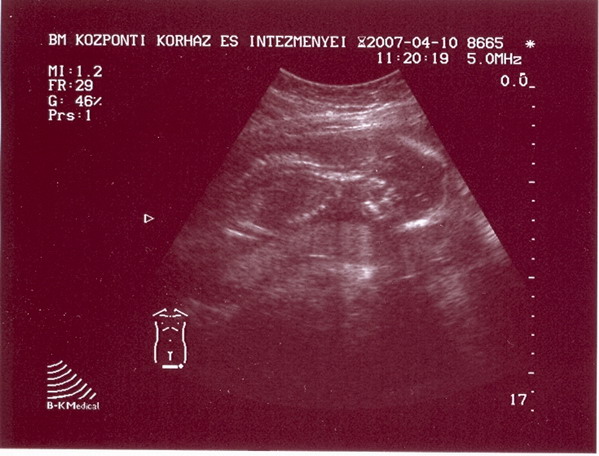

20.5 mm domináns tüszőm megrepedt,mert volt folyadék a méhben,vagy mögött :oops: .Mind1 a lényeg,hogy a gyógyszerhez fűzött reményeim eddig beváltak.

A múltkor a 15.cn -on csak 16.5-17 mm tüszőm volt,most a 15.-on már 20.5 :D

Na minden a legnagyobb rendben van, 2 óra várakozás után jött is a doki, merthogy a BM-ben az UH-t nem orvos csinálja, hanem szonográfus csajszi, és a genetikai UH-t viszont orovos csinálhatja.

Most az mondták 19 + 2, hát én nem tudom, majd kiderül, nagyon hülyén feküdt, lefele bámult logótt a kis feje:), úgyogy halványan sem tudjuk, hogy mi lesz a neme, nem baj a lényeg, hogy minden ok, dobok képet.

A BPD 46, ez a fejekörméret ha jól tudom, az FL (combcsont) pedig 30.